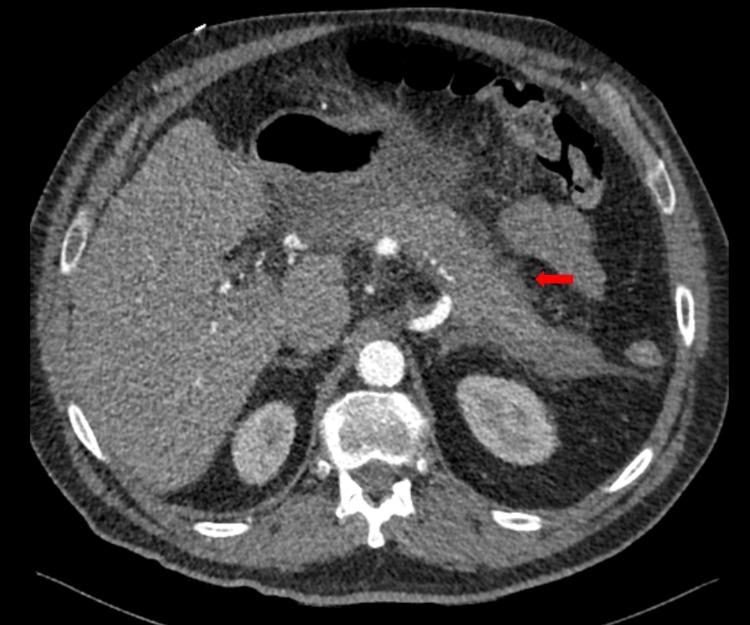

Acute pancreatitis is a common inflammatory disorder of the pancreas. While commonly caused by gallstones, alcohol use, and idiopathic causes, drug-induced acute pancreatitis (DIAP) is an often overlooked etiology that demands careful medication review and clinical vigilance. This case report describes a 72-year-old male patient with a history of hypertension and coronary artery disease who presented with severe epigastric pain radiating to the back, elevated lipase levels, and imaging findings consistent with acute pancreatitis. After excluding common causes such as gallstones, alcohol use, and hypertriglyceridemia, hydrochlorothiazide (HCTZ) was identified as the likely trigger. Discontinuation of hydrochlorothiazide led to clinical improvement and resolution of laboratory abnormalities. This case highlights the importance of considering drug-induced acute pancreatitis, particularly in patients with comorbidities who present with unexplained acute pancreatitis due to their pharmacological therapy.